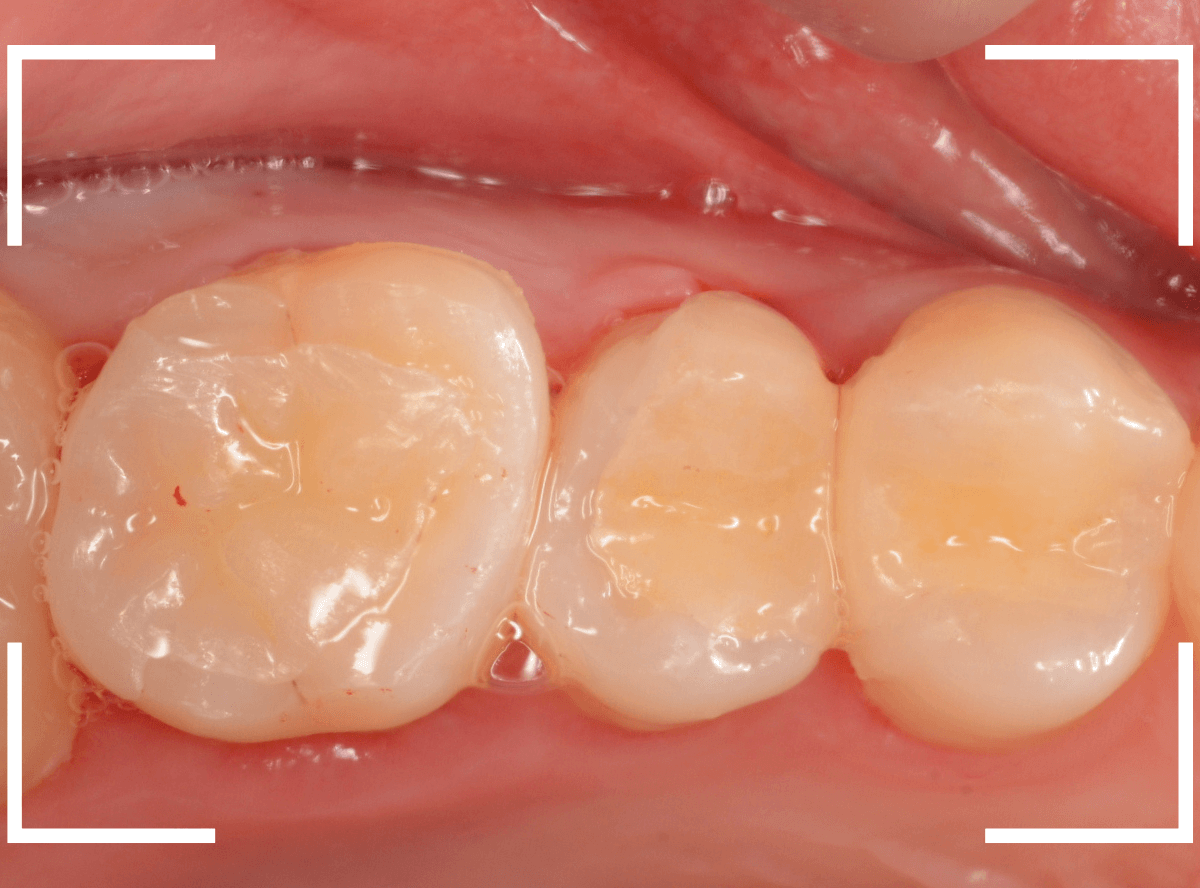

最終setした状態です。

左側の大臼歯2本が、ジルコニア・インレー

右側の小臼歯2本が、E-MAX・インレー

になります。

見た目にほとんど遜色ない仕上がりにできました。